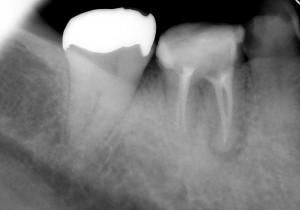

そして今回7ヵ月後・・・

↑7ヵ月後

初診時に溶けていた骨もだいぶ再生されてきました。7ヶ月間症状も特になく、気にすることなく左右バランスよく咬めるとの事。ということで、主治医の先生でかぶせ物を入れてもらうことにしました。まずは一安心(^o^)